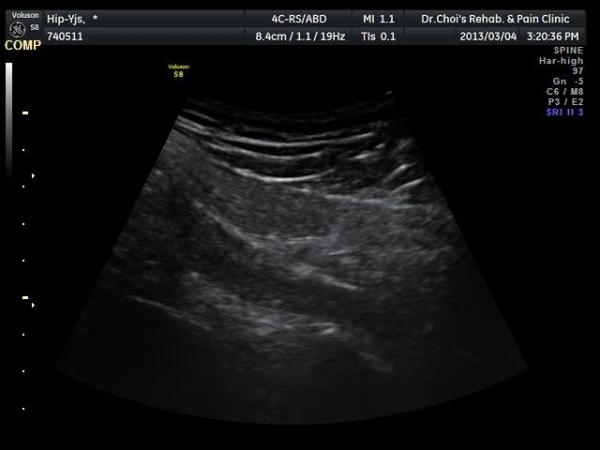

[¾ûµ¢ÀÌ] pirifrormis ±ÙÀ° ÁÖ»çÄ¡·á

ÁÖÁõ»ó

ÁÂÃø ÇÏÁö ´ëÅðºÎ µÚÂÊ ÅëÁõ

ÃÊÀ½ÆÄ °Ë»ç